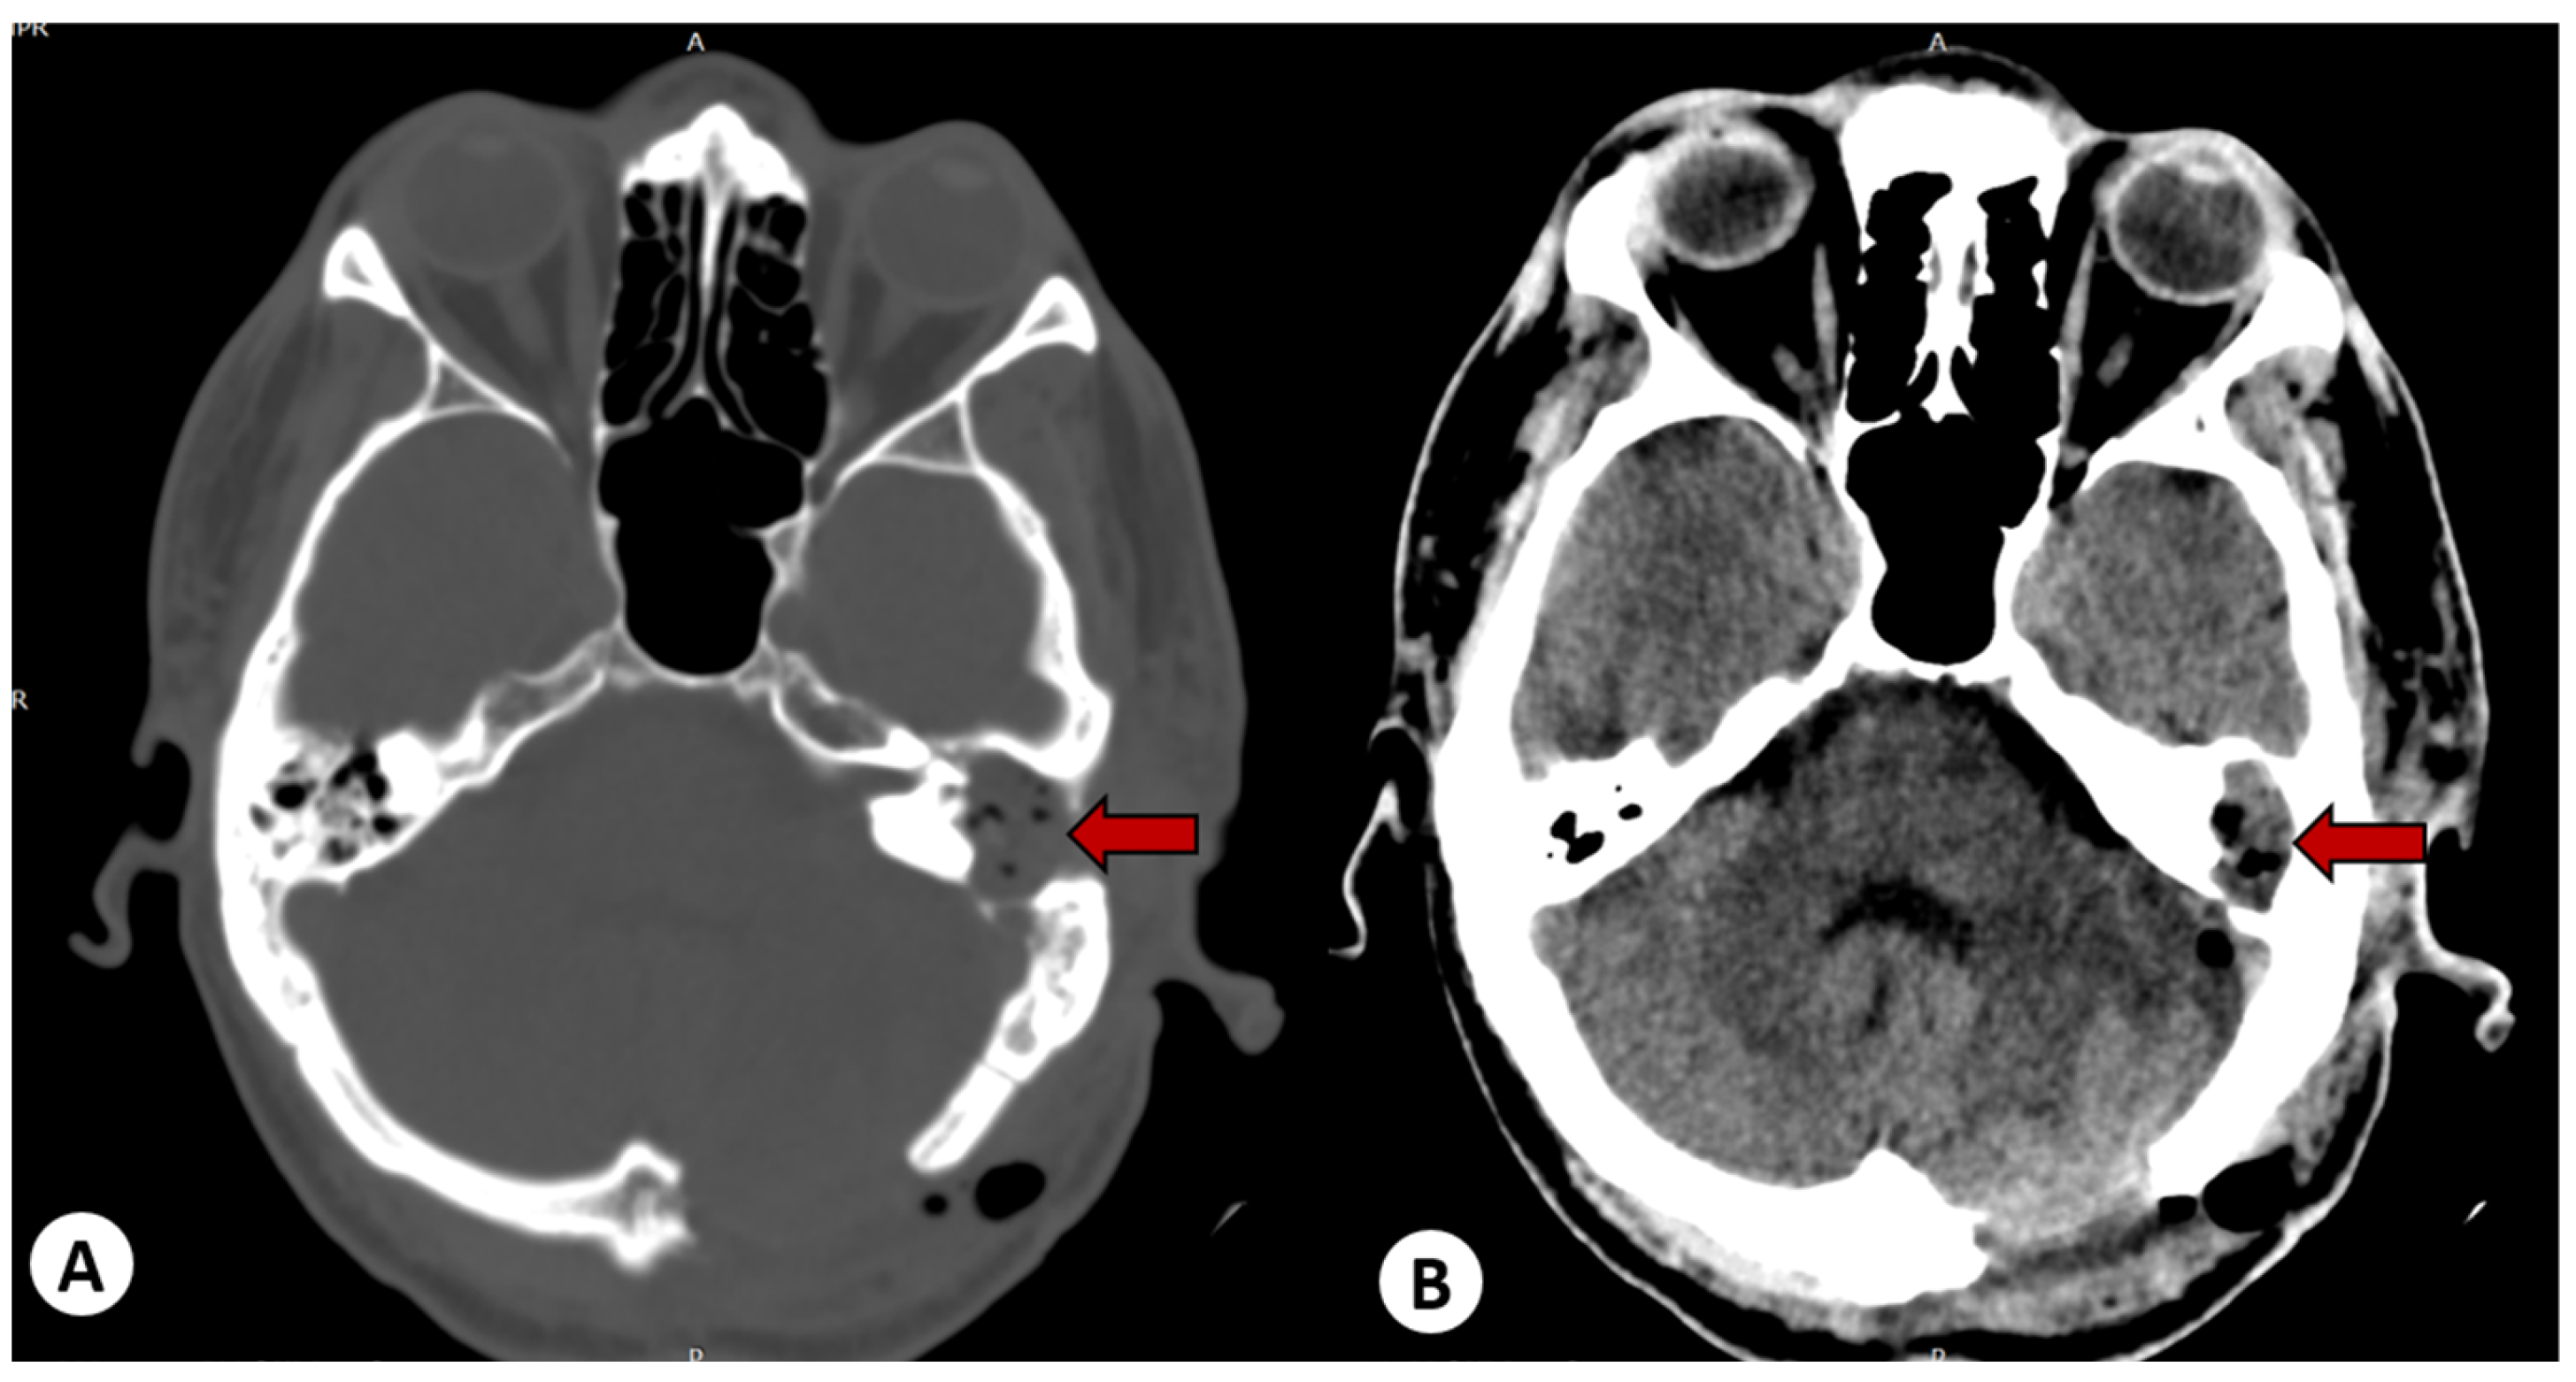

The head CT scan was complemented by magnetic resonance imaging (MRI) with contrast, which revealed a well-defined encapsulated lesion in the left cerebellar hemisphere. The lesion had a heterogeneous structure (hypointense on T1, hyperintense on T2 and FLAIR), with significant diffusion restriction and enhancement on the periphery when contrast was administered. It was associated with perilesional edema and a mass effect that caused compression of the fourth ventricle (measuring 43/36/20 mm—AP/T/CC) as shown in Figure 3.

Figure 3. Axial MRI scan showing a cerebellar abscess in the left hemisphere. In the T1-weighted contrast-enhanced axial section (A), a round mass with peripheral contrast enhancement can be seen. In the T2-weighted axial image (B), its heterogeneous structure is visible, and in the DWI sequence (C), diffusion restriction can be observed; this round mass with peripheral contrast enhancement is in contact with a soft tissue mass from the left middle ear.